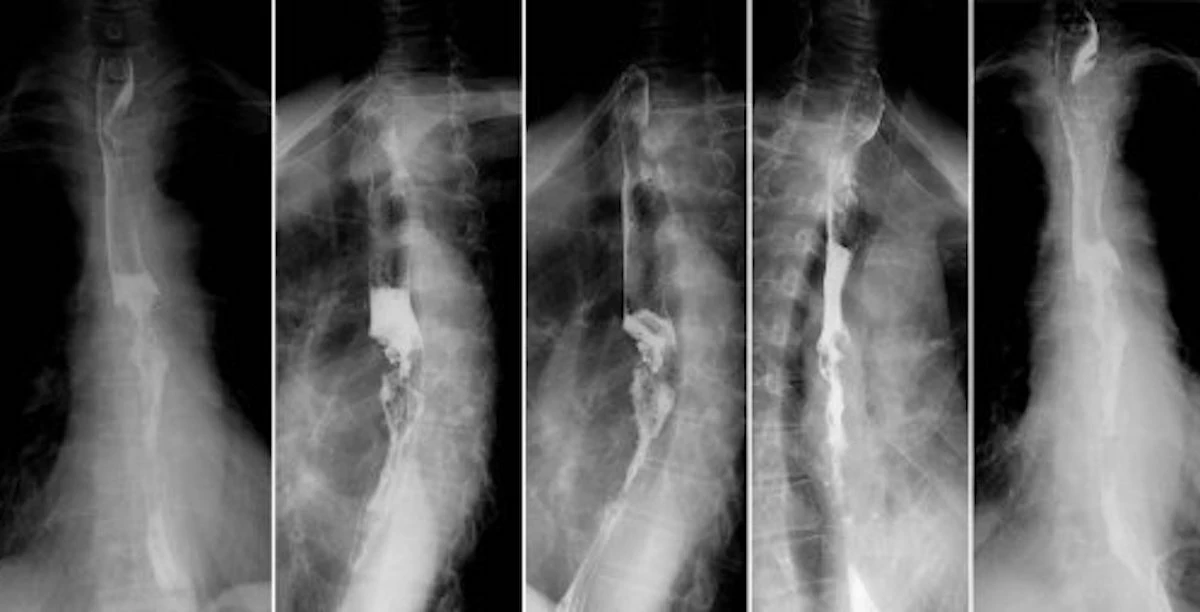

Le complicazioni di un reflusso cronico non trattato possono essere molto serie. “Il reflusso cronico può portare allo sviluppo di condizioni patologiche anche molto gravi quali esofagite, stenosi esofagea, esofago di Barrett che è una lesione pre-cancerosa, fino al tumore dell’esofago”, sottolinea il chirurgo. Per questo è importante rivolgersi a specialisti in grado di interpretare correttamente gli esami e impostare la terapia più adatta.